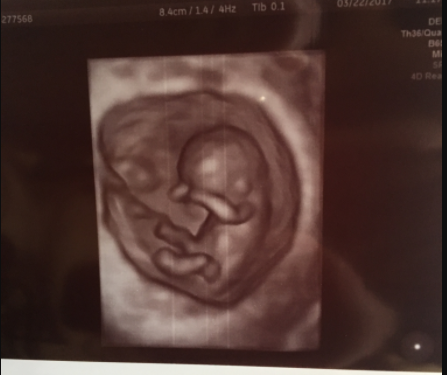

14週0日(14w0d・性別不明)|きなこもっち- さん(32歳)

エコー写真撮影時のエピソード:

病院の都合で、急な転院が決まり転院先で初めてのエコー写真です。新しい病院では、エコーが3Dで見ることができ、立体的な我が子の様子を初めてみて、また動く様子もハッキリと見られてうれしく思ったのを覚えています!

お姉ちゃんになる娘は、まだ分からないようですが、なんとなく感じているのか時々お腹に顔を当てています。まるで、指しゃぶりをしているようなお腹の中の我が子♪早く会いたいです!